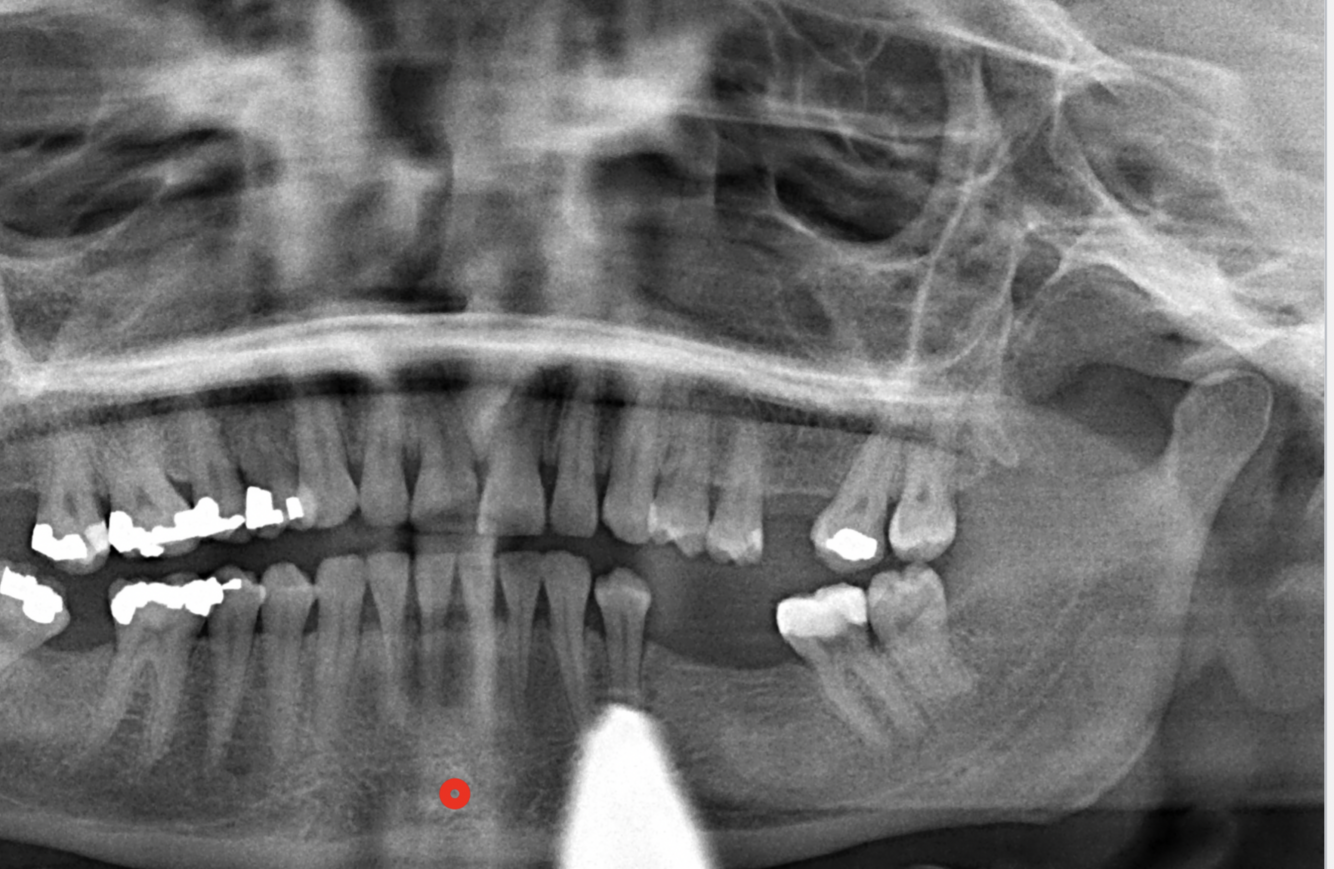

What does the red indicate in the following image?

Lingual foramen